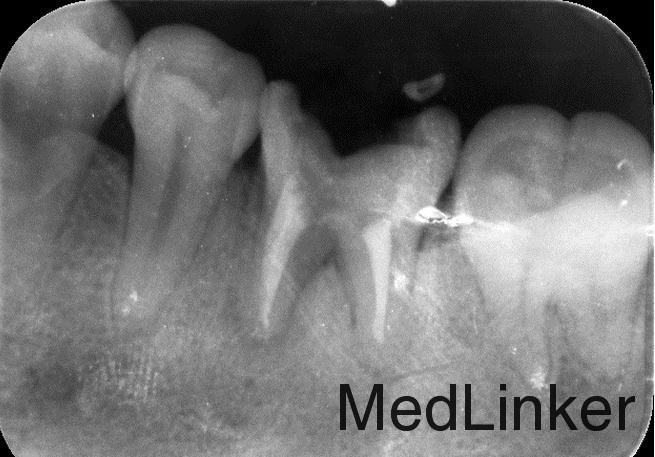

曲面断层片检查

根管治疗加高嵌体修复